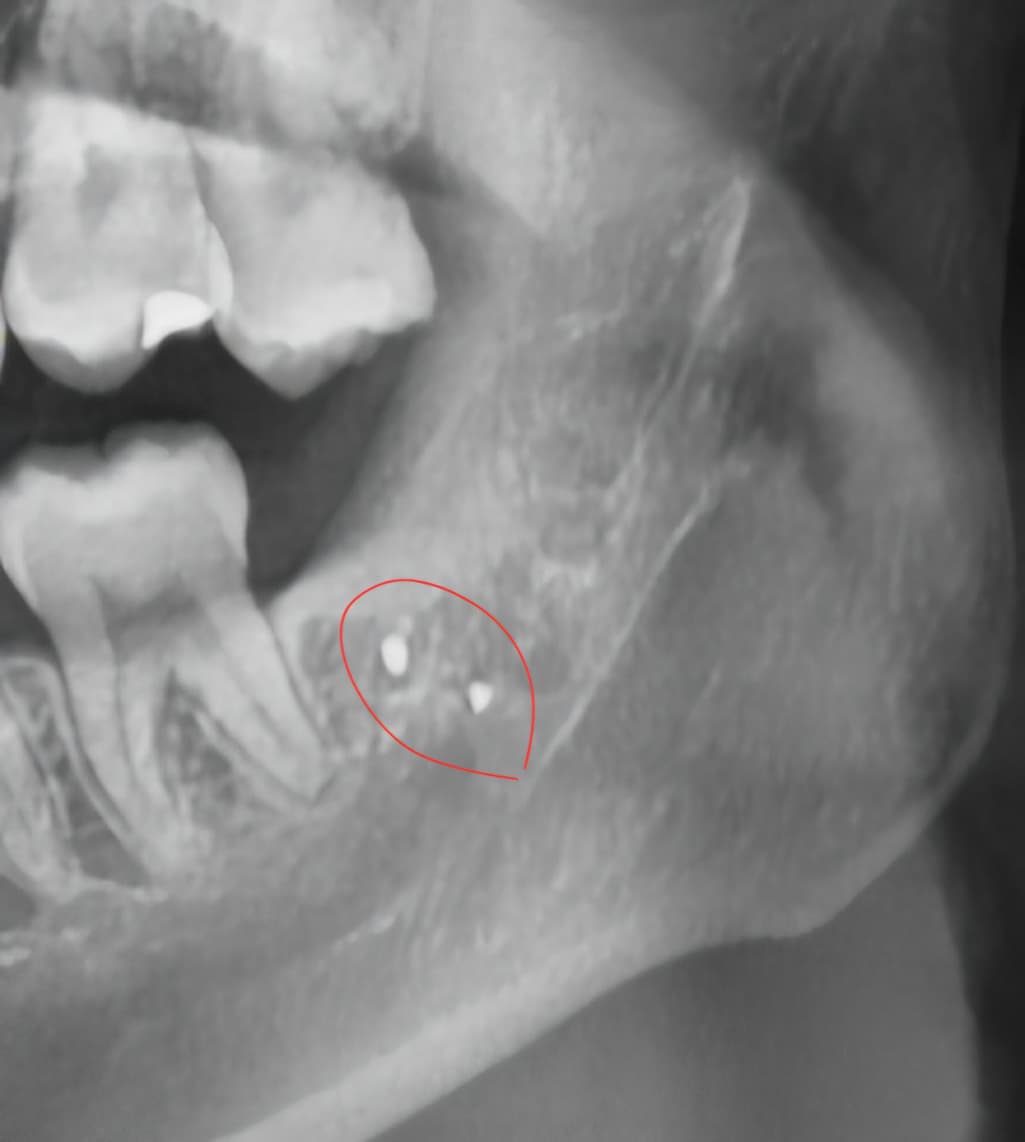

사랑니 뽑은 뒤 잇몸에서 금속 발견되었어요

사랑니 뽑은 지 9개월이 넘었고, 같은 치과에서 엑스레이를 찍었더니 사진과 같은 게 있었습니다

사랑니를 발치하는 과정에서 아말감이 탈락되어 들어갔거나 도구가 파절되었다면 해당부위에 방사선 사진상처럼 보일수 있습니다. 감염이 되지 않았다면 문제가 되지 않으며 무리하게 제거를 하려고 하면 신경손상등이 발생할수 있습니다.

증상이 없다면 그냥 두셔도 크게 문제가 되진 않습니다. 오히려 저걸 제거하려다가 신경손상 가능성이 있어 보입니다.

1 .작은 이물질이고 특별히 그동안 이물질을 일으키지 않았다면 이로 인해 문제가 발생할 확률은 낮습니다

1. 저걸 빼기 위해 잇몸뼈를 삭제하고, 신경을 건드릴 가능성이 있기 때문에 득보다 실이 클 수 있습니다